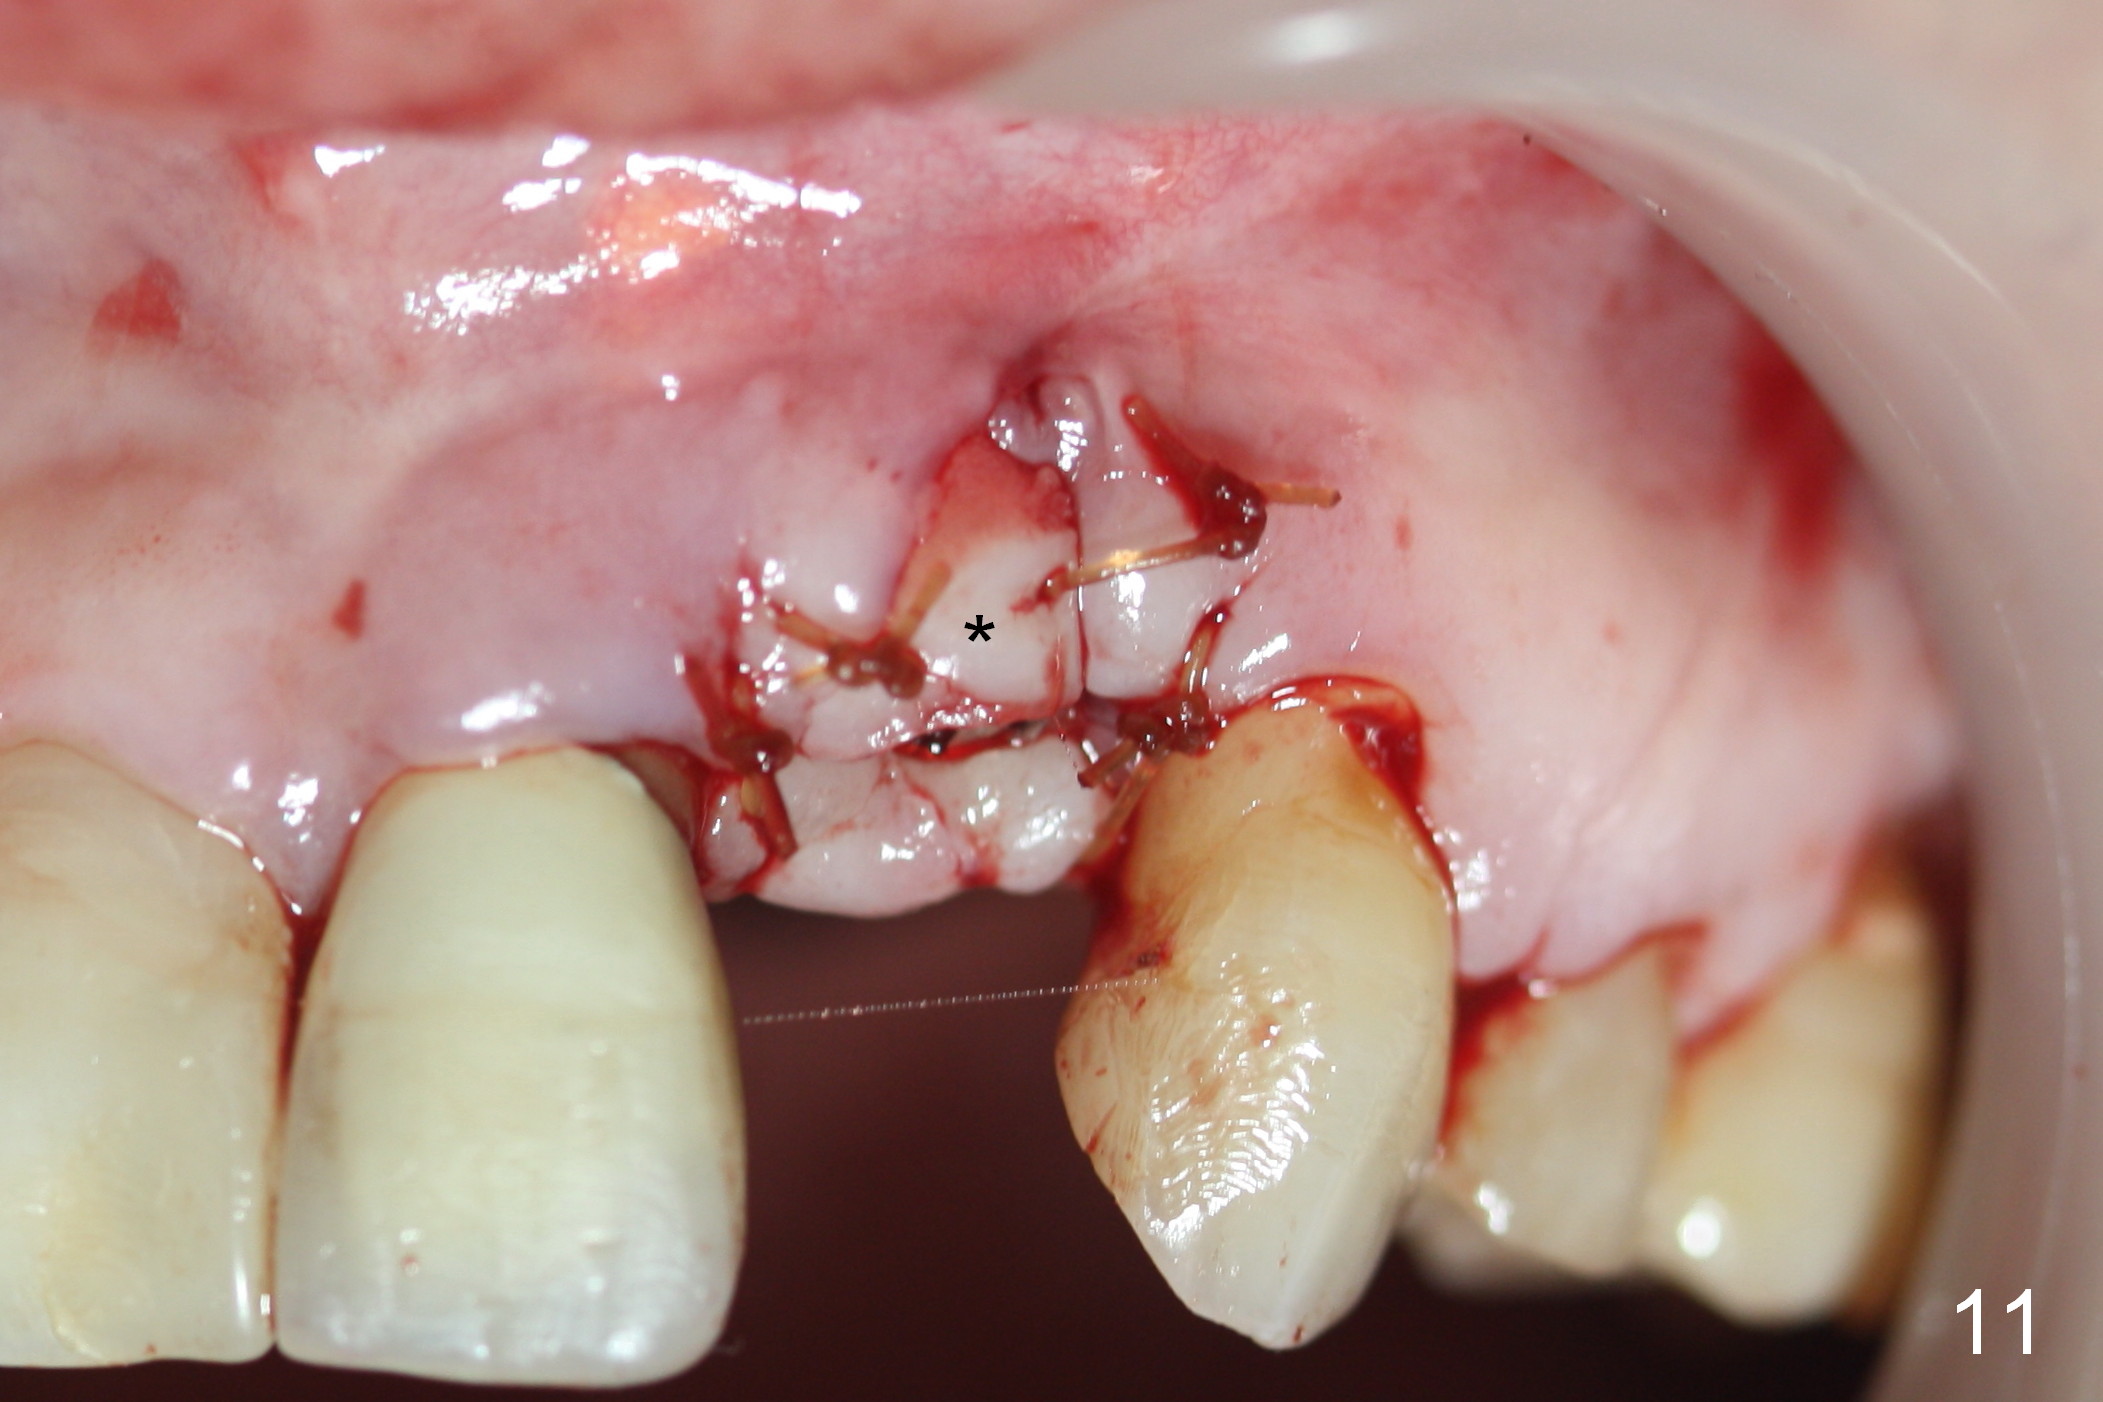

As expected, there is midbuccal tissue deficiency (Fig.9,10: 2 months postop). After discussion, a free gingival graft from the palate is placed (Fig.11,12 *). Two weeks later, the graft sloughs (Fig.13). A pedicled flap is designed (Fig.14) and transferred to repair the defect (Fig.15,16).